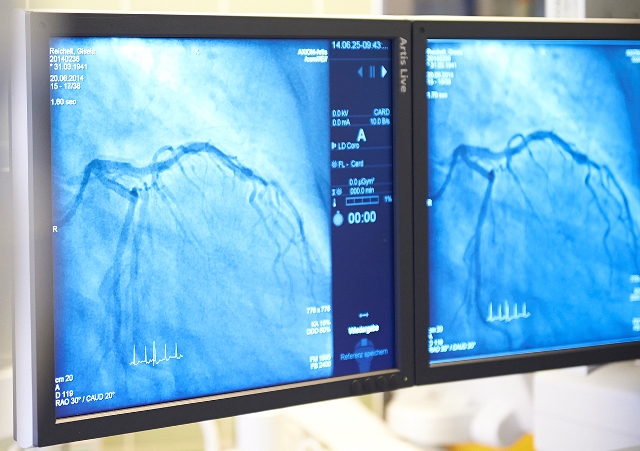

Monitore im Herzkatheterlabor (Foto: St. Vinzenz)

Darüber hinaus haben die Besucher des Herztages 2015 die einmalige Gelegenheit, hinter die Kulissen zu blicken und eine simulierte Herzkatheter-Untersuchung im OP-Saal mit zu verfolgen. Eine Besichtigung des Aufwachraums, sowie die Möglichkeit, seinen eigenen Blutzucker, Blutdruck und Puls messen zu lassen, besteht ebenfalls. Wer möchte, kann auch sein Herz mithilfe der Echokardiographie, das heißt mithilfe des Ultraschalls, untersuchen und ein EKG schreiben lassen.

Bildunterschrift: Monitore im Herzkatheterlabor